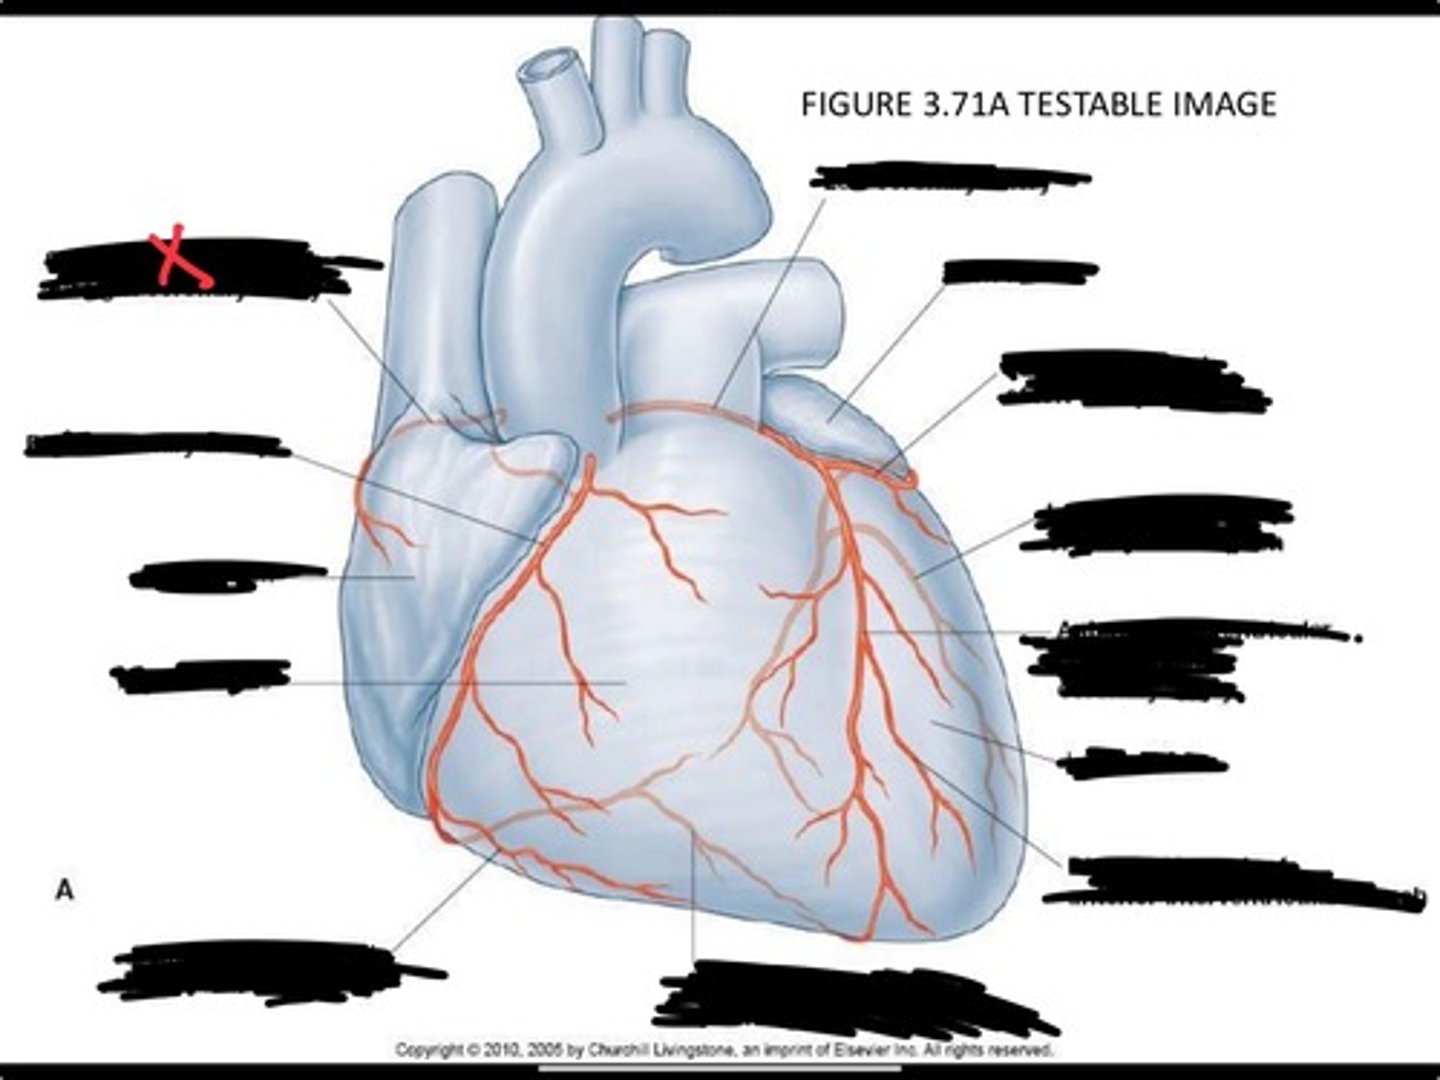

Posterior interventricular branch of right coronary artery

Right arginal branch of coronary artery

Right ventricle

Right atrium

Right coronary artery

Sinu-atrial nodal branch of right coronary artery

Left coronary artery

Left auricle

Circumflex branch of coronary artery